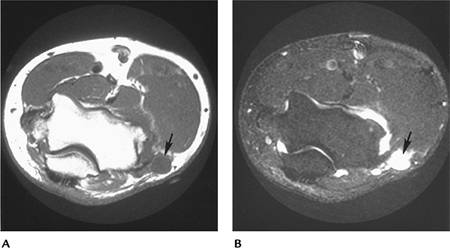

![]() |

FIGURE 8-18 Axial T1- (A) and fast spin-echo T2-weighted (B) with fat suppression and sagittal fast spin-echo T2-weighted (C) fat-suppressed images demonstrate an undisplaced osteochondritis dissecans of the capitellum (arrow).